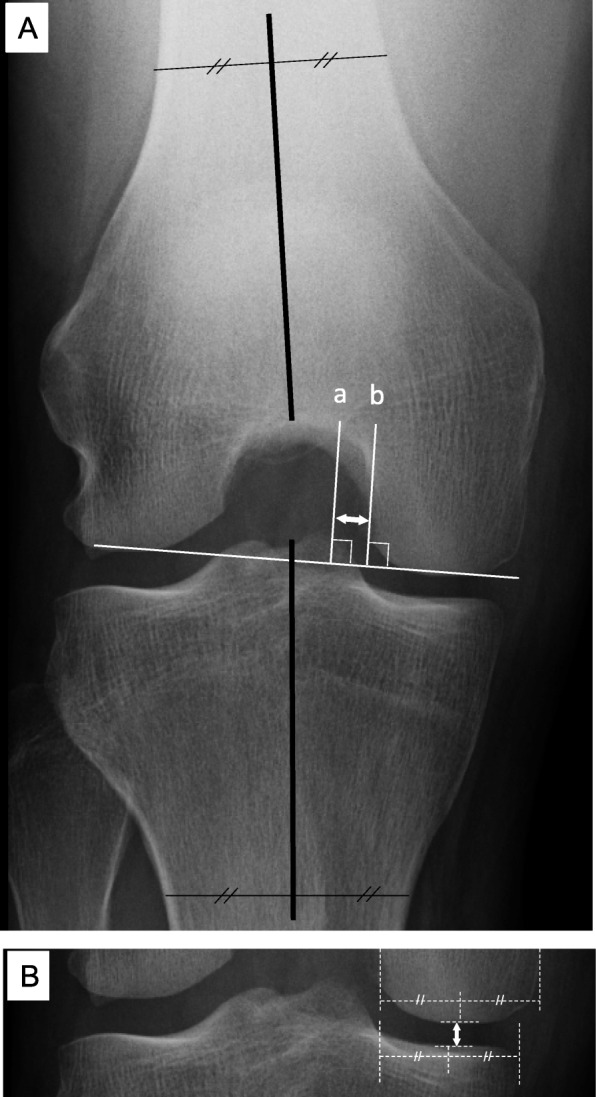

Fig. 2.

a Measurement methods for the distance from the medial tibial eminence (MTE) to the medial femoral condyle (MFC) and the femorotibial angle (FTA) during weight bearing with the knee flexed at 45°. The MTE line (a) and MFC line (b) are drawn perpendicular to the line tangent to the medial and lateral femoral condyles, along the lateral edge of the MFC. The distance between the MTE and the MFC is then measured (white double-headed arrow). b Measurement of the medial joint space (MJS) width using the Rosenberg view. The MJS is measured from the center of the MFC to the center of the medial tibial plateau (white double-headed arrow). The weight-bearing FTA, with the knee flexed at 45°, is measured (black lines) (a). A best fit line is drawn through the midpoints of the outer cortex of both the femur and tibia, and the FTA is defined by the angle at their intersection

Evaluation of the distance between the MTE and MFC

On the Rosenberg view, the MTE line was drawn perpendicular to the line tangent to the medial and lateral femoral condyles, and the MFC line perpendicular to the line tangent to the medial and lateral femoral condyles, along the lateral edge of the MFC. The distance between the MTE and MFC was measured (Fig. 2a). To compare this distance, the same methods were used for the contralateral knee.

Evaluation of the MJS

The MJS was measured from the center of the MFC to the center of the medial tibial plateau (Fig. 2b) [21].